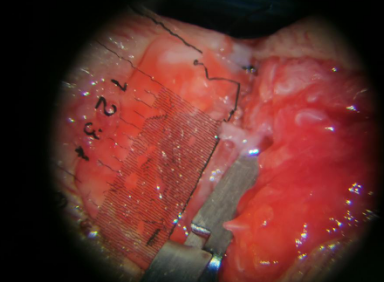

潘医生医疗团队借助医院最新引进的徕卡显微镜,在放大8至16倍条件下使用12-0进口显微缝合线为张大姐一一吻合动脉、静脉、神经。其中最细的血管直径只有0.3mm,刚刚可以勉强缝合。缝合血管的显微缝合线如果脱离了显微镜,使用肉眼几乎是看不见的,难度可想而知。还好,手术比较顺利。

术中